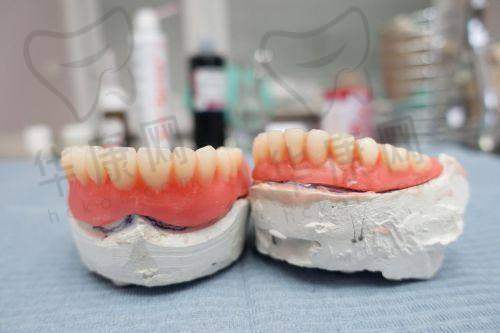

成都医大口腔医院全口种植牙之术后修复

术后的几天,我的口腔有点肿胀和疼痛,但都在能接受的范围内。按照医生的嘱咐,我按时吃消炎药、冰敷,注意饮食,尽量吃软的食物。医院还会定期打电话回访我的修复情况,提醒我按时来复诊。每次复诊,医生都会仔细检查我的伤口愈合情况和种植体的稳定性。随着时间的推移,我的伤口慢慢愈合,种植体也和牙槽骨逐渐结合。

成都医大口腔医院全口种植牙之诊疗成效

经过一段时间的修复,我的全口种植牙终于完成了。现在,我可以像正常人一样吃饭、说话,再也不用担心牙齿缺失的问题了。种植牙的外观和真牙特别相似,几乎看不出来是假牙。而且,它的咀嚼功能也良好,吃什么都香。我真的特别满意这次的诊疗成效,感觉自己又找回了自信。